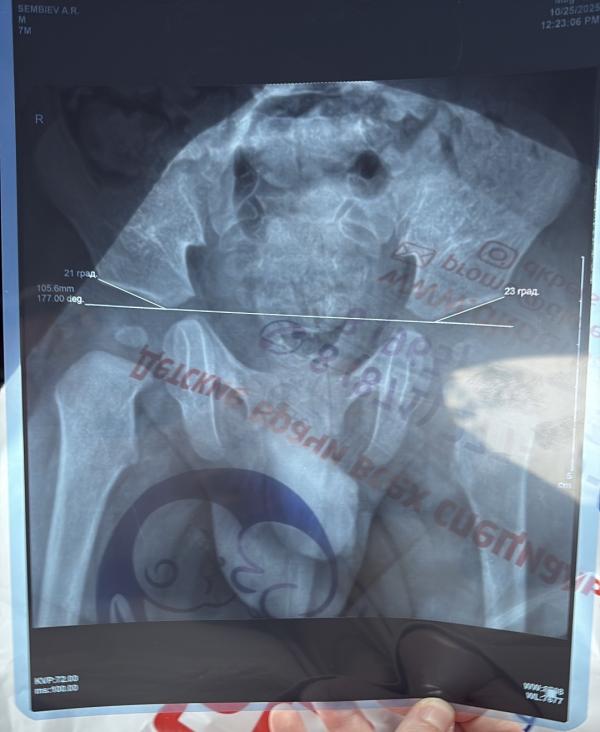

У кого была такая проблема? Дисплазия тазобедренных суставов,какие бывают проблемы у ребенка?🥲